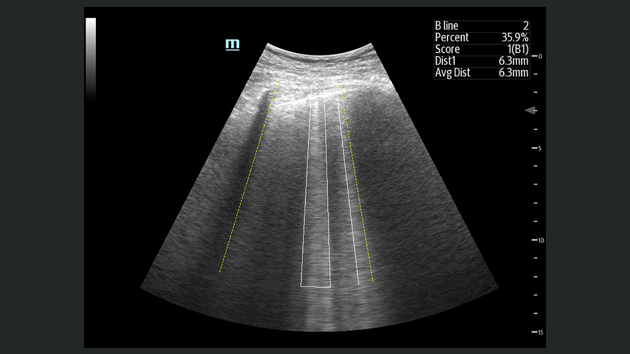

Obrazy kliniczne